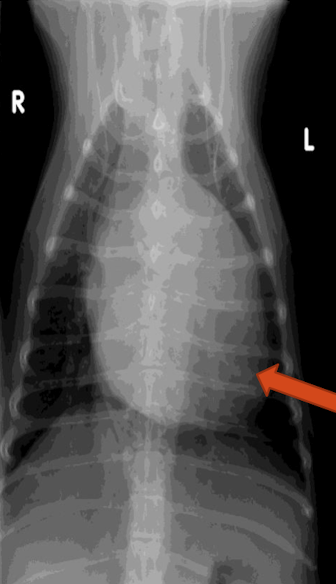

What is the arrow pointing to?

Enthesophyte